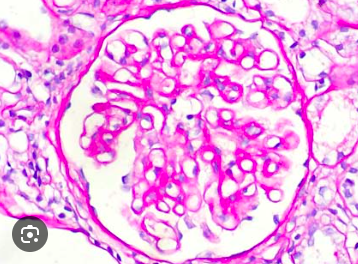

¿Qué es esto?

A

Glomérulo normal